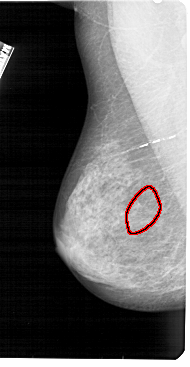

A_1393_1.LEFT_CC

LEFT_CC LINES 4891 PIXELS_PER_LINE 2611 BITS_PER_PIXEL 12 RESOLUTION 43.5 OVERLAY

FILE: A_1393_1.LEFT_CC.OVERLAY

TOTAL_ABNORMALITIES 1

ABNORMALITY 1

LESION_TYPE CALCIFICATION TYPE AMORPHOUS DISTRIBUTION SEGMENTAL

ASSESSMENT 4

SUBTLETY 2

PATHOLOGY BENIGN

TOTAL_OUTLINES 1

BOUNDARY